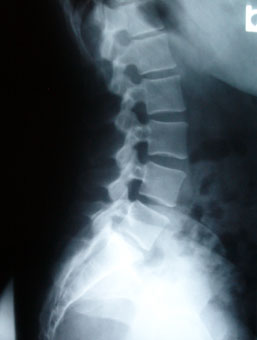

Spondylolisthesis - Wikipedia, The Free Encyclopedia

Degenerative spondylolisthesis is a disease of the older adult that develops as a result of facet arthritis and joint remodeling. X-ray of a grade 4 spondylolisthesis at L5-S1 with spinal misalignment indicated. Degenerative disc disease; Spinal disc herniation; Facet joint arthrosis; ... Read Article

Spinal Stenosis Due To Advanced Degenerative Disc Note the advanced L5‐S1 disc space narrowing the endplate hypertrophy and retrolisthesis of L5 on sacrum. The ... Access Doc

OBSERVATION Examination: MRI Lumbar Spine Without Contrast ...

OBSERVATION Examination: MRI Lumbar Spine without Contrast Clinical indication: At the L2-3 level, moderate degenerative facet hypertrophy is present. L5-S1: Disc space narrowing with disc desiccation and vacuum disc phenomenon. ... Retrieve Document